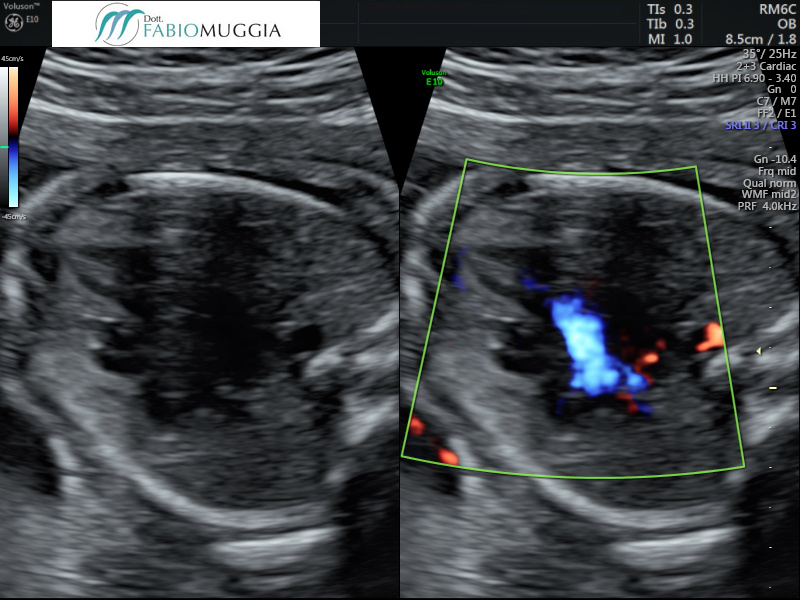

Infatti, parliamo anche dello studio del percorso del sangue all’interno delle cavità cardiache. Ciò oggi è reso possibile dalla tecnologia Doppler colore, specialmente nelle sue versioni più raffinate, come quelle che permettono lo studio dei flussi con alta definizione (HD-Flow) e con la possibilità di determinare anche la direzione del flusso stesso durante l’esame (il “codice colore” che associa la direzione del flusso di sangue con un colore specifico, rosso o blu, nelle sue varie gradazioni, secondo una ben precisa scaletta indicata sul monitor, in un riquadro in alto a sinistra).

Cuore fetale 20 settimane - 4 camere apicale

Si notano tutte le principali strutture cardiache nella loro regolare conformazione anatomica.